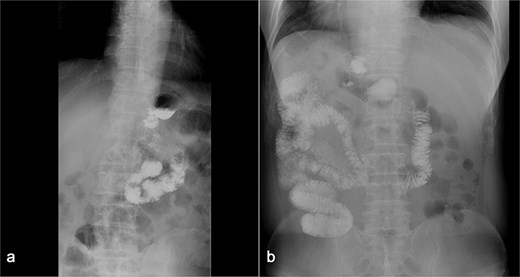

(a) Displays preoperative Gl contrast, while (b) depicts postoperative Gl contrast.

Endoscopy/imaging: Patent GGA without stenosis/leakage (Fig. 4). Normal antral peristalsis and pyloric function (Fig. 5).